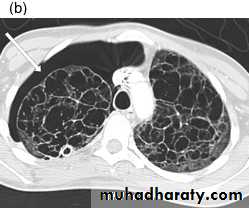

PNX in

Diseased lungDiseases of the Pleura Dr.Mustafa Nema. Baghdad College of Medicine 2013

PNX inCystic lung

disease

CT adds information regarding the presence or absence of pleural fluid and underlying pulmonary disease.Diseases of the Pleura Dr.Mustafa Nema. Baghdad College of Medicine 2013

emphysematous bulla (not PNX)